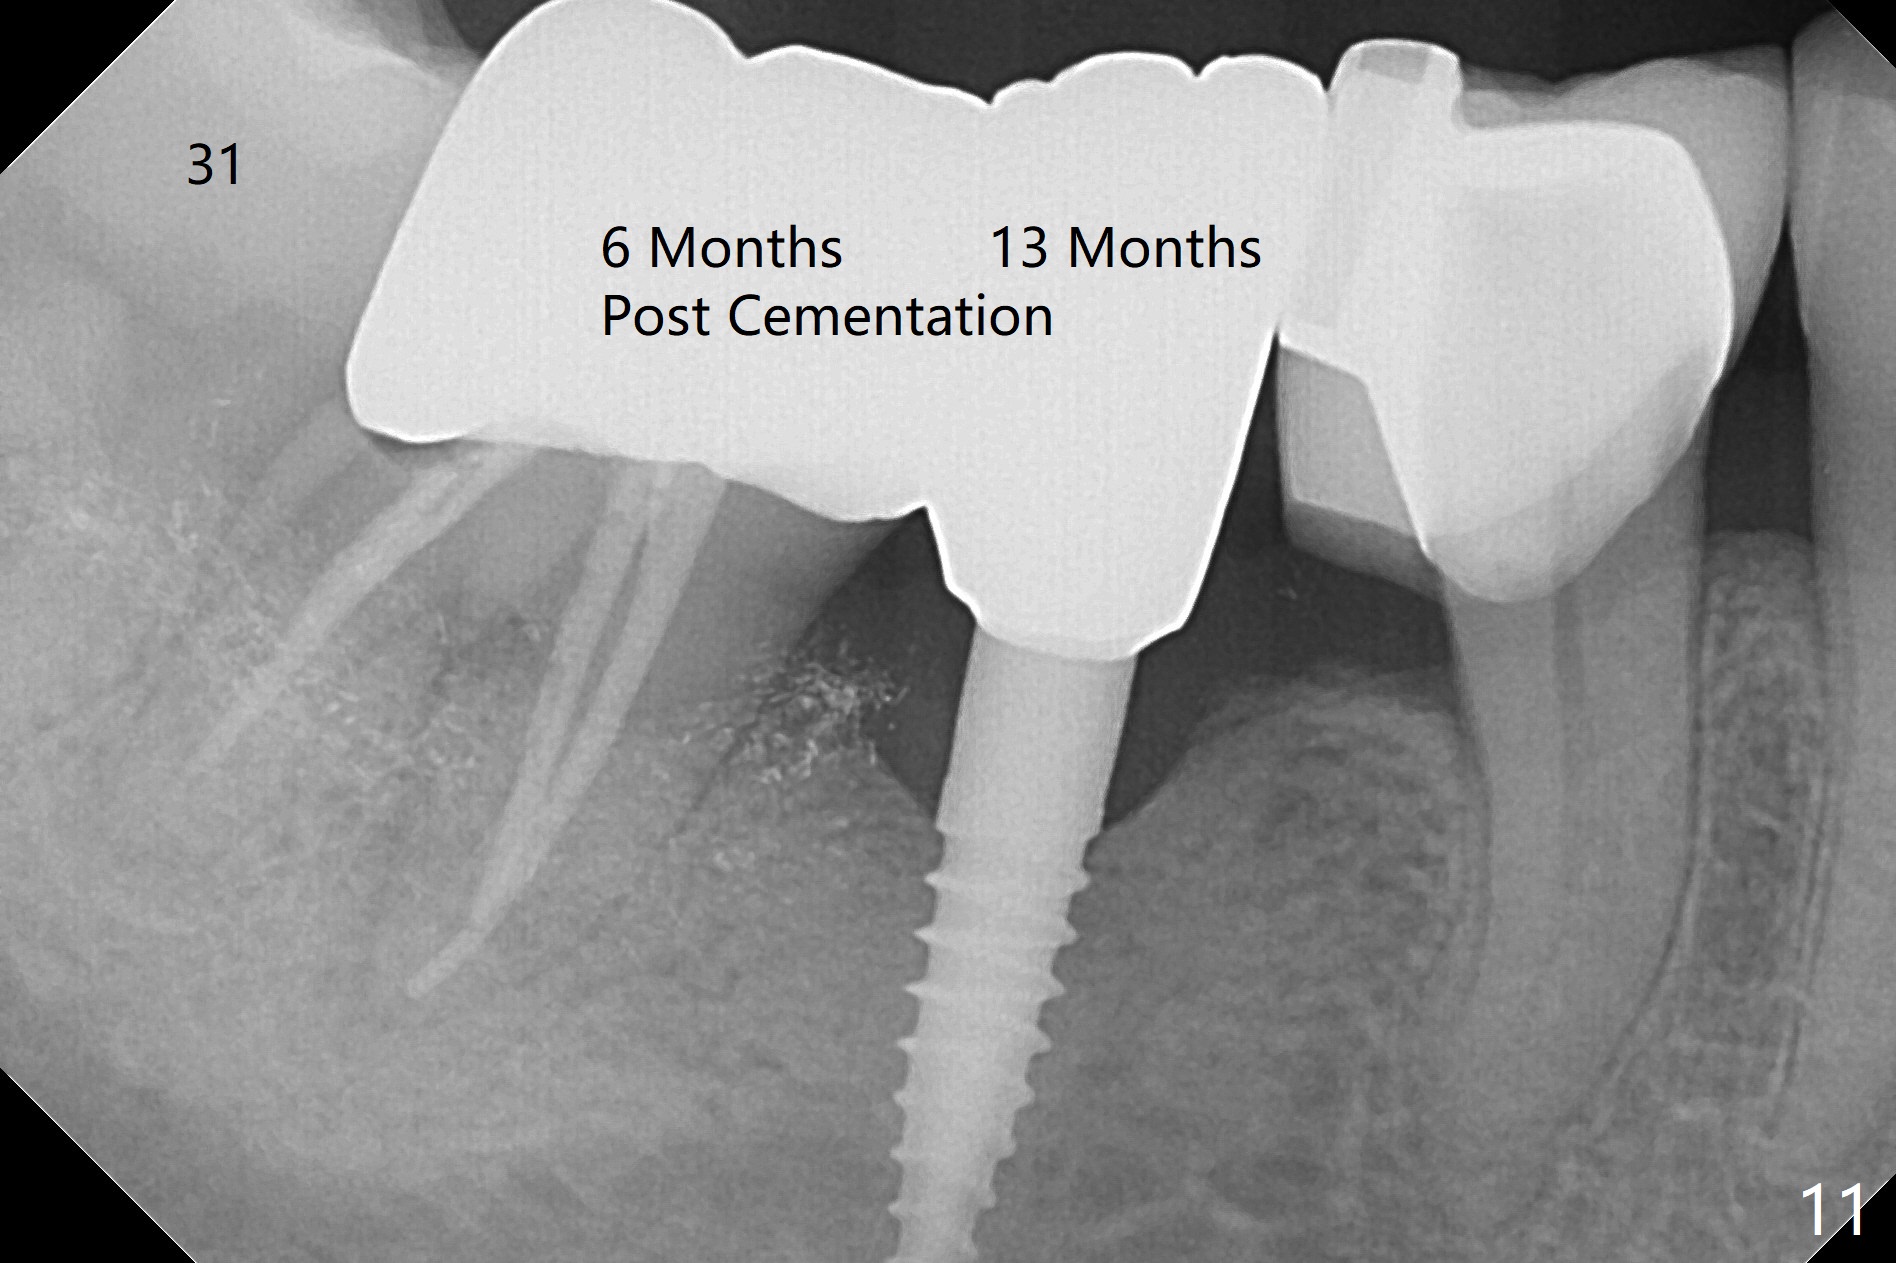

There is a space underneath the pontic at #30 (Fig.1 *), the basis for food impaction. After sectioning between the pontic and the posterior retainer, the pontic is removed from the anterior retainer with an attachment (Fig.2 *). The initial depth of osteotomy is 10 mm following ridge top reduction (Fig.3). A 3x10(4) mm 1-piece implant is placed with >50 Ncm; to reduce possibility of crown dislodgement from the implant, the retainers will be kept with modification of the proximal surfaces as shown by curved lines in Fig.4. Periodontal dressing is applied after suturing. There is no postop paresthesia. The periodontal dressing remains in place 2 weeks postop because of engagement into the attachment slot and undercuts (Fig.5). The patient returns 3 months postop; after minor contour adjustment (Fig.6 red curved line), impression is taken. The permanent crown is temporarily cemented (3.5 months postop) in case of food impaction due to the distal overhang of the tooth #29 (Fig.7). In fact the patient returns 4.5 months post cementation with right TMD (muscle relaxant prescribed) and food impaction, although there is no bone resorption (Fig.8,9). It appears that the crown at #29 needs to be redone, while porcelain will be added to the mesial surface of the one at #30 (Fig.10 red lines). In fact the crown at #30 is redone because of loose proximal contact with #31; there is no bone resorption 13 months post cementation (Fig.11). Bone resorption remains unnoticeable 28 months post cementation (Fig.12,13).